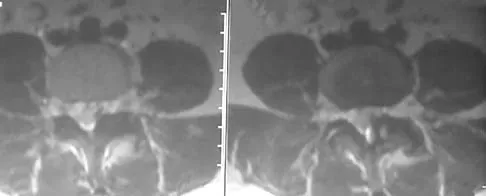

A 78-year-old woman undergoes her third lumbar decompression and fusion from L3 to L5 without complication. On the morning of postoperative day 3, examination reveals painless, flaccid weakness of both lower extremities. She also has an absent bulbocavernous reflex and a mild saddle paresthesia. MRI scans of the lumbar spine are shown in Figures 26a and 26b. What is the most appropriate management at this time?

Explanation